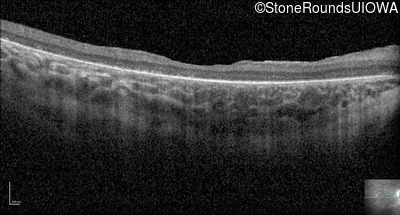

Optical Coherence Tomography - Right - 20/100

Exemplar / OCT Stack

OCT Stack